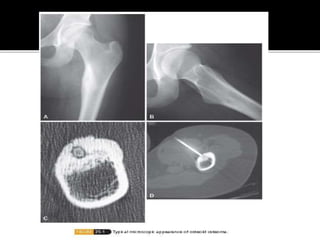

 Common in 2nd-3rd decades

 M:F – 3:1

 Common sites – Lower extremities – long

bones, Spine

 Typical pain – worse at night, relieved by

NSAIDS.

 Joint – Stiffness, swelling, contracture

Spine – Scoliosis

 Imaging – Cortical radiolucent nidus <1.5cm

with marked cortical thickening (Xray/CT).

Marked uptake onTC99 bonescans

 Histology –Trabeculae surrounded by loose

fibrovascular tissue

 Treatment

- NSAIDS

- Burr DownTechnique

- RF ablation